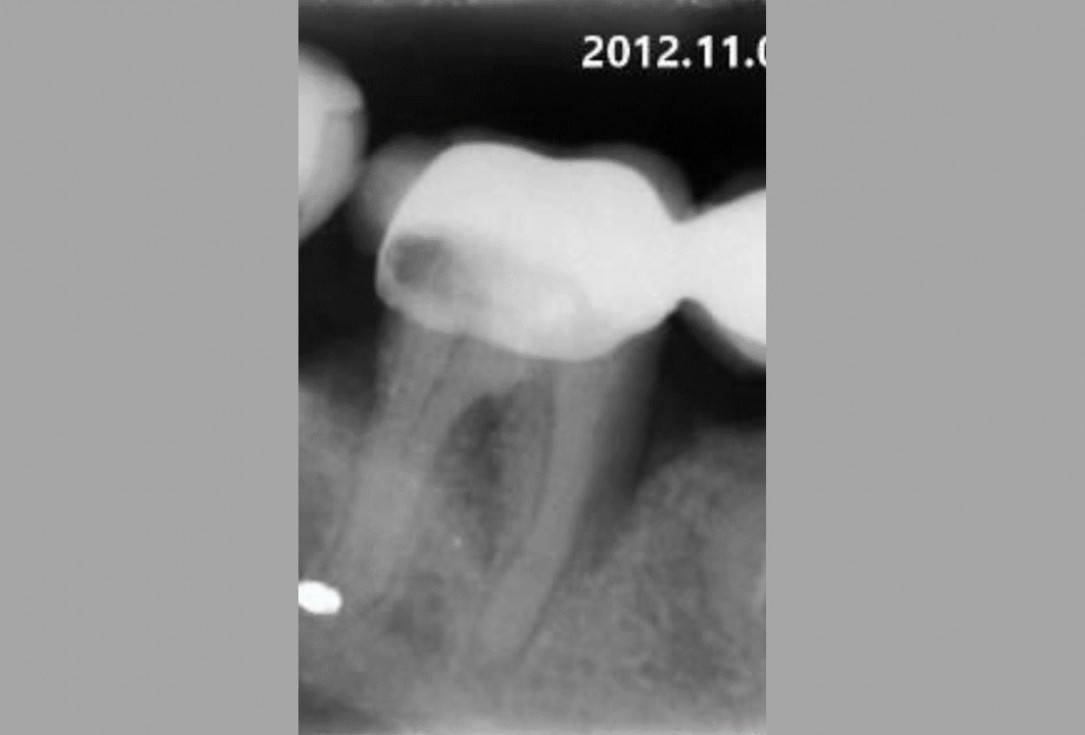

01/06 - Pre-operative radiographic view.Intrabony defect treated using Straumann® Emdogain®, cerabone® and Jason® membrane - Dr. D. B. Hangyási

Pre-operative radiographic view.